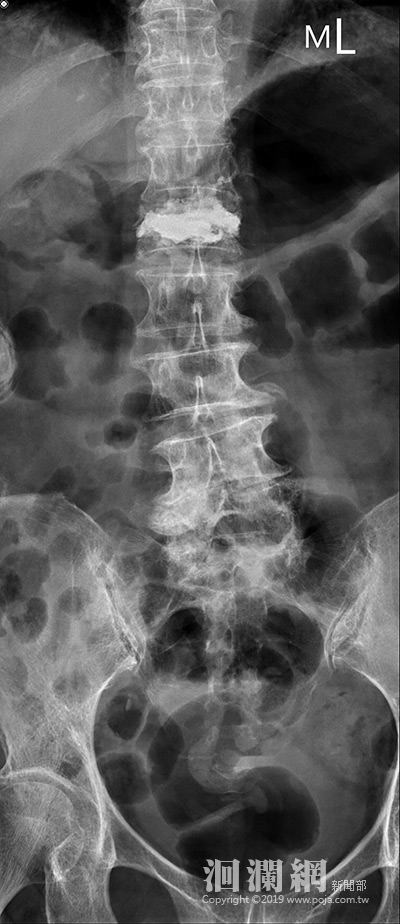

九十六歲的陳姓阿嬤,原本身體硬朗,一月間卻因在家中跌倒,腰推痛得讓她動彈不得,只能躺在床上忍受疼痛,沒想到過完農曆新年,疼痛症狀歷經一個月不但沒有改善,反而加劇,兒女帶她到花蓮慈院麻醉疼痛科就醫,希望能緩解她的疼痛,但經檢查,臨床麻醉暨疼痛科主任王柏凱醫師發現陳阿嬤是腰椎骨折,轉介給洪祥益主任醫治。

熟悉這項術式的洪祥益指出,這個手術不需要全身麻醉,以局部麻醉加神經阻斷術,可以全程無痛完成脊椎灌骨水泥手術;過程風險低、手術傷口小,約只有一個針頭大小,不須縫合、不必拆線,手術時間更是縮短約半小時就可以完成。